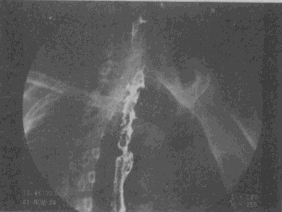

2.男,38歲,鋇劑示食管壁張力減低,蠕動減弱,鋇劑排空延遲,并見食管下段有串珠狀充盈缺損影,首先應考慮

A.食管下段靜脈曲張

B.食管黏膜下平滑肌瘤

C.反流性食管炎

D.食管裂孔疝

E.食管癌

正確答案:A解題思路:食管的串珠狀充盈缺損影為食管靜脈曲張的典型表現(xiàn)。